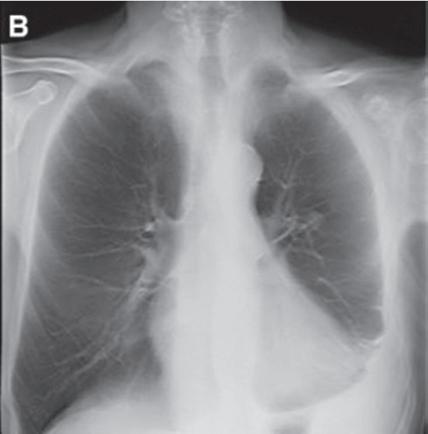

Most DECT datasets can be used to generate additional virtual monoenergetic images (typically between 40 and 60 keV [kilo electron volts]) that have high-contrast enhancement because they are close to the k-edge of the iodine. To minimize contrast streak artifacts and image noise in larger patients, higher keV images ( >70 keV) may be necessary. Iodine or pulmonary blood volume images represent material decomposition images (obtained from subtracting water from contrast-enhanced DECT images) that provide information on distribution of iodine in the lungs or remainder of the chest depending on the selected settings. The absolute iodine concentration expressed as milligrams per milliliter can be calculated from pulmonary blood volume images (Fig. 1.10). One can also generate water or virtual noncontrast images from contrast-enhanced

DECT by subtracting iodine from the image datasets to differentiate calcium, hemorrhage, or high-protein content from iodinated contrast (Fig. 1.11). The DECT technique also allows generation of higher keV images, which can help reduce artifacts with metallic implants or prostheses (Fig. 1.12).

FIGURE 1.11 Virtual noncontrast image. A soft tissue density mass is seen in the subcarinal region on the 140-kV image (A). On the virtual noncontrast (VNC) image (B), after iodine substraction, there is no change in the density of the subcarinal mass, and therefore there is no evidence for enhancement. This mass is consistent with a nonenhancing bronchogenic cyst.